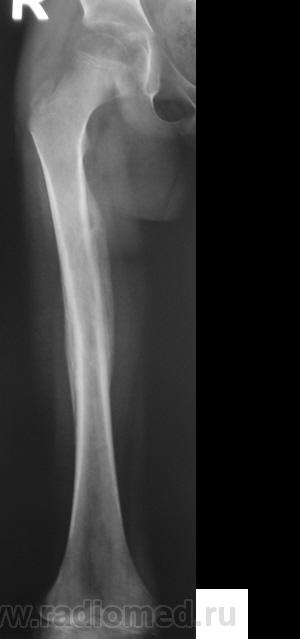

Пациент направлен на конрольное рентгенологическое исследование средней трети бедренной кости с целью оценки консолидации. Ранее - первичный снимок пациент был направлен на рентгенографию средней трети бедра, что и было сделано. Но, при производстве "контроля" рентгенолаборанты захватили тазобедренный сустав в прямой проекции, и возникли неясные сомнения по поводу головки, да и вообще...

Интересная дискуссия. Жаль с опозданием увидел (однако же, много времени уходит, пока всё на сайте просмотришь). На мой взгляд, патологии головки нет, без фрагментации, проекционно пересекается с тенью обызвествляемого Y-хряща. Под головкой медиально, несомненно, есть остеопороз, придающий нечеткость картине. Впрочем, регионарный остеопороз имеет место вследствие закономерной атрофии после иммобилизации. Сюда же наслаивается субстрат т.н. фигуры серпа, еще не оформленный. Впадина нормальная. Кость срослась - замечательно, всем бы такие результаты. Реабилитация обязательна.

Из-за выраженного остеопороза бедра и тазовых костей, некоторые контуры теряются… да ещё кисты в шейке и головке мерещатся. Томограмма сама просится. Вот разве что Ola-la на обмен согласна.